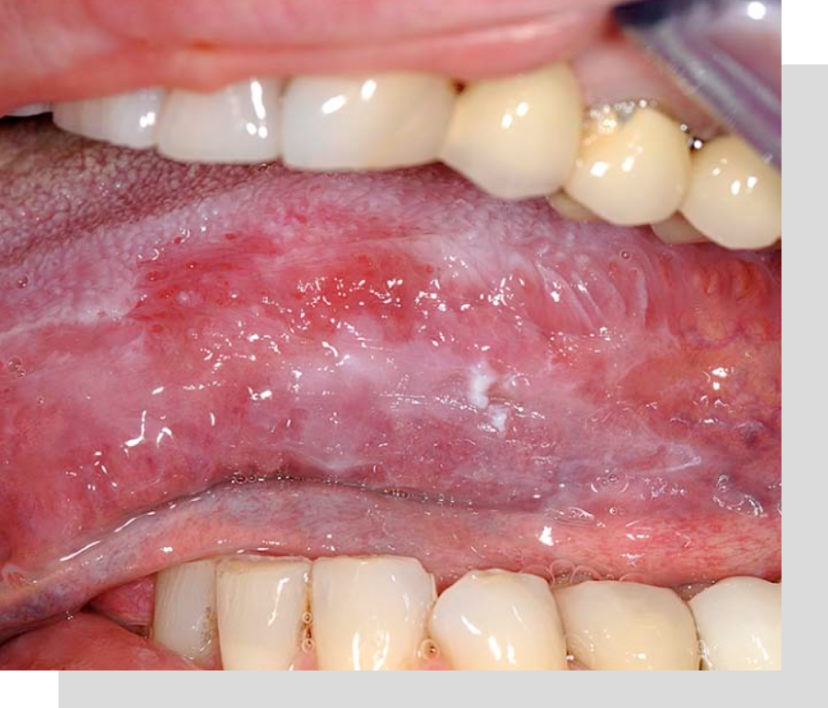

Biopsias

Se realizan biopsias ante lesiones orales sospechosas que duren mas de 15 días, o que tengan algún aspecto anormal, procedimiento en donde se toma una pequeña muestra para estudio de las lesiones.